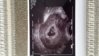

Dzwonilam do Provity według waszych rad i załamanie nie ma już miejsc na program rządowy; ( będziemy u dr. Cholewy i podejdziemy do ICSI prywatnie. Doradzcie jak sie przygotowac co można zrobić aby się udało;/